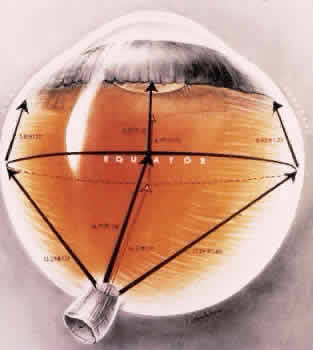

Fig. 16. Typical and reticular cystoid degeneration found immediately behind the

ora serrata and about enclosed ora bay near cut edge of calotte. Posteriorly, note

the conspicuous vascular pattern of degeneration (seen as

gray background), finely stippled surface pattern, and angular free

margins (related to limitation by surface vessels). Fig. 16. Typical and reticular cystoid degeneration found immediately behind the

ora serrata and about enclosed ora bay near cut edge of calotte. Posteriorly, note

the conspicuous vascular pattern of degeneration (seen as

gray background), finely stippled surface pattern, and angular free

margins (related to limitation by surface vessels).